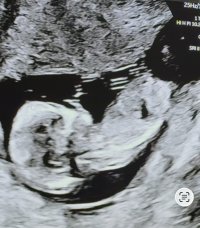

JenteNoen som vil gjette her? uke 13+1Vis vedlegget 472328

Tipper også jenteNoen som vil gjette her? uke 13+1Vis vedlegget 472328